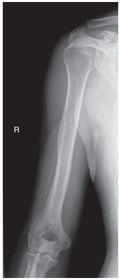

Which projection/position is this? PA Lateral Humerus

Projection/position? Lateral Humerus